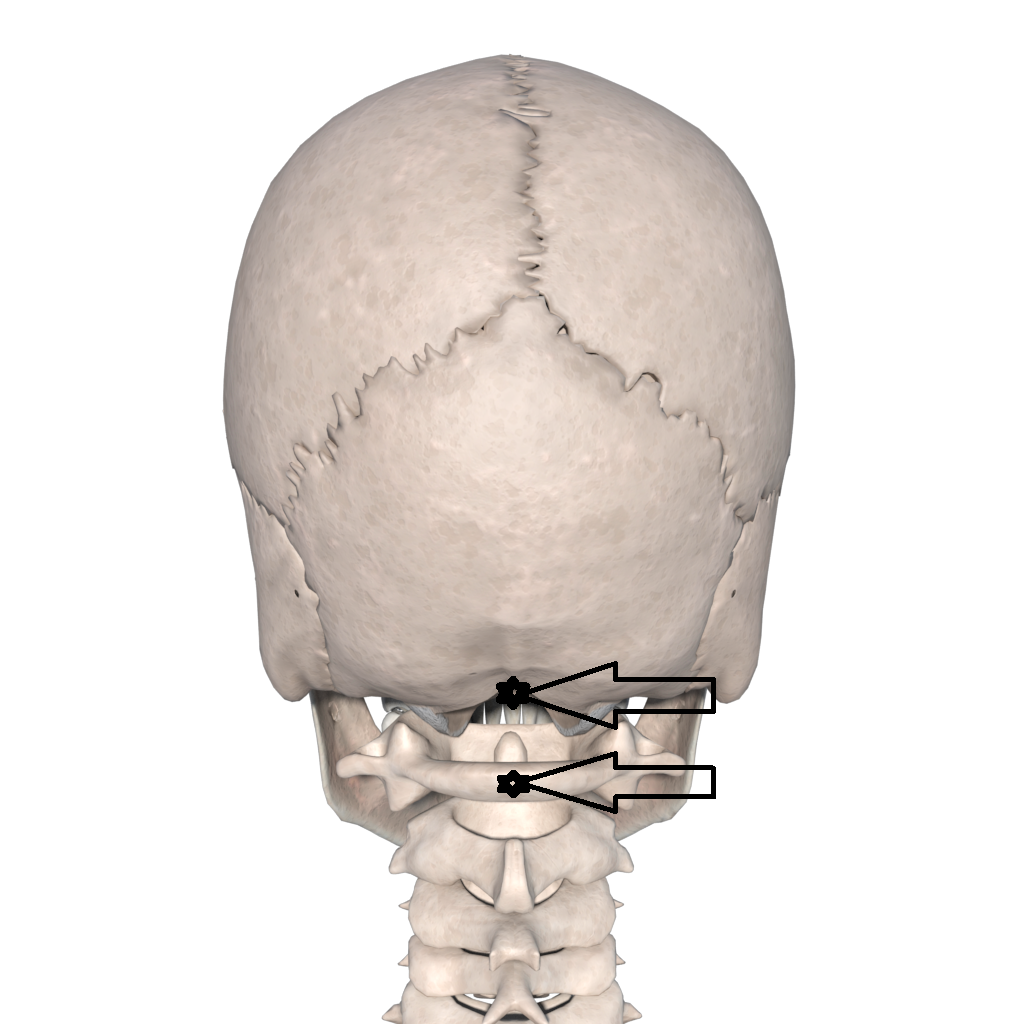

枕骨大孔疝位置图片

②枕骨大孔疝(transforamen magna herniation),为小脑扁桃体及延髓经

图1-15枕骨旋转会伴随着枕骨大孔附近肌肉起止点的压痛.复位手法.